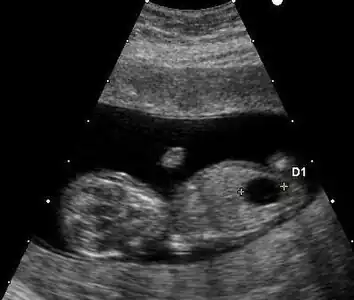

Ultrasound

Prenatal ultrasound can be used to screen for Down syndrome. Findings that indicate increased chances when seen at 14 to 24 weeks of gestation include a small or no nasal bone, large ventricles, nuchal fold thickness, and an abnormal right subclavian artery, among others.[113] The presence or absence of many markers is more accurate.[113] Increased fetal nuchal translucency (NT) indicates an increased possibility of Down syndrome picking up 75–80% of cases and being falsely positive in 6%.[114]

Ultrasound of fetus with Down syndrome showing a large bladder

Enlarged NT and absent nasal bone in a fetus at 11 weeks with Down syndrome